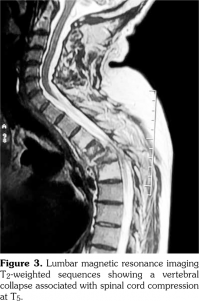

Laboratory examination revealed a slightly elevated C-reactive protein level (16 mg/L) and erythrocyte sedimentation rate (40 mm). Serum levels of calcium, albumin and phosphorus were within the normal range. Blood cell counts, liver tests, and renal function were unremarkable. Blood cultures, urinanalysis, tumor markers, and serodiagnosis for brucella were negative. Tuberculosis skin test was negative. Spine magnetic resonance imaging showed low T1, high T2 signal and contrast enhancement in the T4/T5 and L3 vertebral body and in the T4/T5 disk (Figure 1). Sacroiliac joints were normal. Computed tomography-guided biopsy of the T4/T5 disc demonstrated nonspecific inflammation and culture of this specimen was negative. Computed tomography scan of the sternoclavicular joints revealed hyperostosis and erosions involving the sternum as well as medial end of clavicle (Figure 2). Clavicular biopsy showed irregular sclerotic trabeculae. Human leukocyte antigen B27 typing was positive.

In our patient, the diagnosis of spondylodiscitis related SAPHO syndrome was established based on the medical history of palmoplantar pustulosis and computed tomography-guided biopsy which showed negative results for metastatic tumor or infection associated with hyperostosis, erosions involving sternum and medial end of clavicle and the presence of human leukocyte antigen B27. Indeed, in adults with SAPHO syndrome, prevalence of the human leukocyte antigen B27 is high and varies between 13 to 30%.(1) In our patient, the main differential diagnosis was ankylosing spondylitis. However, the medical history of palmoplantar pustulosis and the presence of hyperostosis involving sternum and medial end of clavicle were against this diagnosis. The involvement of the sternoclavicular joint is uncommon, occurring in less than 4% of patients with ankylosing spondylitis.(8)